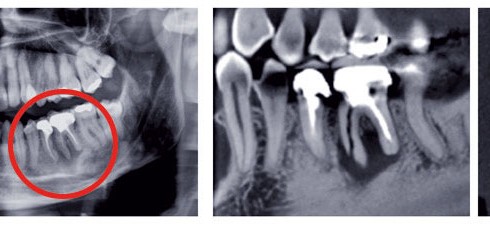

Article réservé à nos abonnés Apport de l’imagerie cone beam en endodontie

L’exploration radiographique du réseau canalaire radiculaire est une nécessité en endodontie. La visualisation de l’endodonte et de son environnement osseux...

L’imagerie conventionnelle (2D) Argentique ou numérique, ses deux versions ne diffèrent que par la nature du capteur (film ou récepteur...